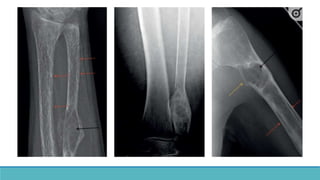

• Cortical bone erosion – Phalanges

•Most sensitive site : Radial aspects of

middle phalanges of index and middle

fingers.

• Tufts of distal phalanges.

•Acrosteolysis – distal phalanges, Outer

clavicle, pubic symphysis, sacroiliac joints,

proximal medial cortex of tibia, proximal

humeral shaft, ribs and femur.

• Cortical boneerosion – Phalanges •Most sensitive site : Radial aspects of middle phalanges of index and middle fingers. • Tufts of distal phalanges. •Acrosteolysis – distal phalanges, Outer clavicle, pubic symphysis, sacroiliac joints, proximal medial cortex of tibia, proximal humeral shaft, ribs and femur.